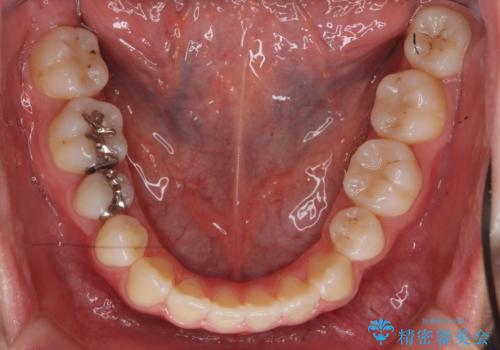

受け口 親知らずを取り込む矯正治療

- 高校生で来院。受け口が主訴でした。

下の小臼歯を抜歯しましたが、その代わり下の親知らずを残して咬ませたので、歯の数は変わっていません。